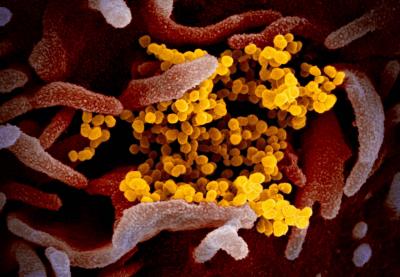

स्कॉटलँड स्कूल ऑफ लाईफ सायन्सनी कोरोना व्हायरसच्या काही प्रिंट्स फोटो दाखवले आहेत. त्यात असं दिसून येत आहे कोरोना व्हायरसचं आतड्यांवर फक्त संक्रमण होत नसून कोरोना आतड्यांमध्ये वेगाने पसरत जातो.

माणसाच्या शरीराला संक्रमित करून आतड्यांपर्यंत पोहोचत असलेला कोरोना व्हायरस पांढऱ्या रंगाचा दिसतो. कोरोनाचे निरक्षण करण्यासाठी शास्त्रज्ञांनी अल्ट्रा पॉवरफुल मायक्रोस्कोपचा वापर केला.

शरीरातील कोरोना व्हायरसची माहिती देणारे हे फोटो ३० ते ५० गीगाबाईट्सचे आहेत. स्कूल ऑफ लाईफ सायन्सचे क्वारंटाईन सेल बायोलॉजी प्रोफेसर यांनी सांगितले की, कोरोना व्हायरस आतड्यांपर्यंत पोहोचून शरीराचं नुकसान करत असतो. आतड्यांमध्ये व्हायरसची संख्या वेगाने वाढत जाते.